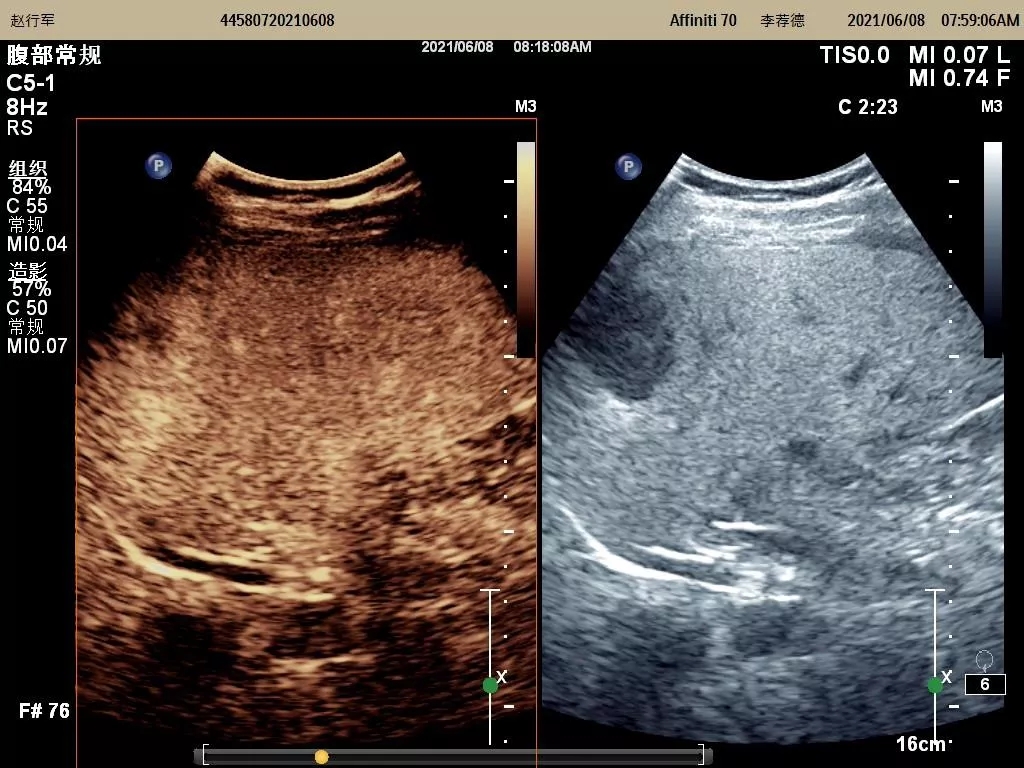

自我院功能检查科成功开展市内首例超声造影检查技术后,近期又开展了多例脏器(包括肝脏、甲状腺、乳腺、淋巴结等)超声造影术。该技术的全面成熟开展,标志着我院超声造影检查技术再上新台阶,必将进一步推动陇南地区超声医学专业的发展。

图为开展的肝脏超声造影检查